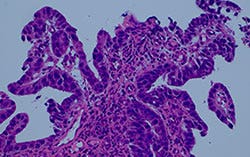

Figure 4: Comparison of a halogen lamp with filter versus a generic LED and a True Color LED

Comparison of halogen lamp + filter and True Color LED

After a series of discussions on these issues with pathologists, we determined that the new LED light source complied with the standard values defined as Olympus’ original evaluation colors and achieved the “same color” as the halogen lamp with filter illumination that we were striving for.

Comparison of halogen lamp + filter and generic LED